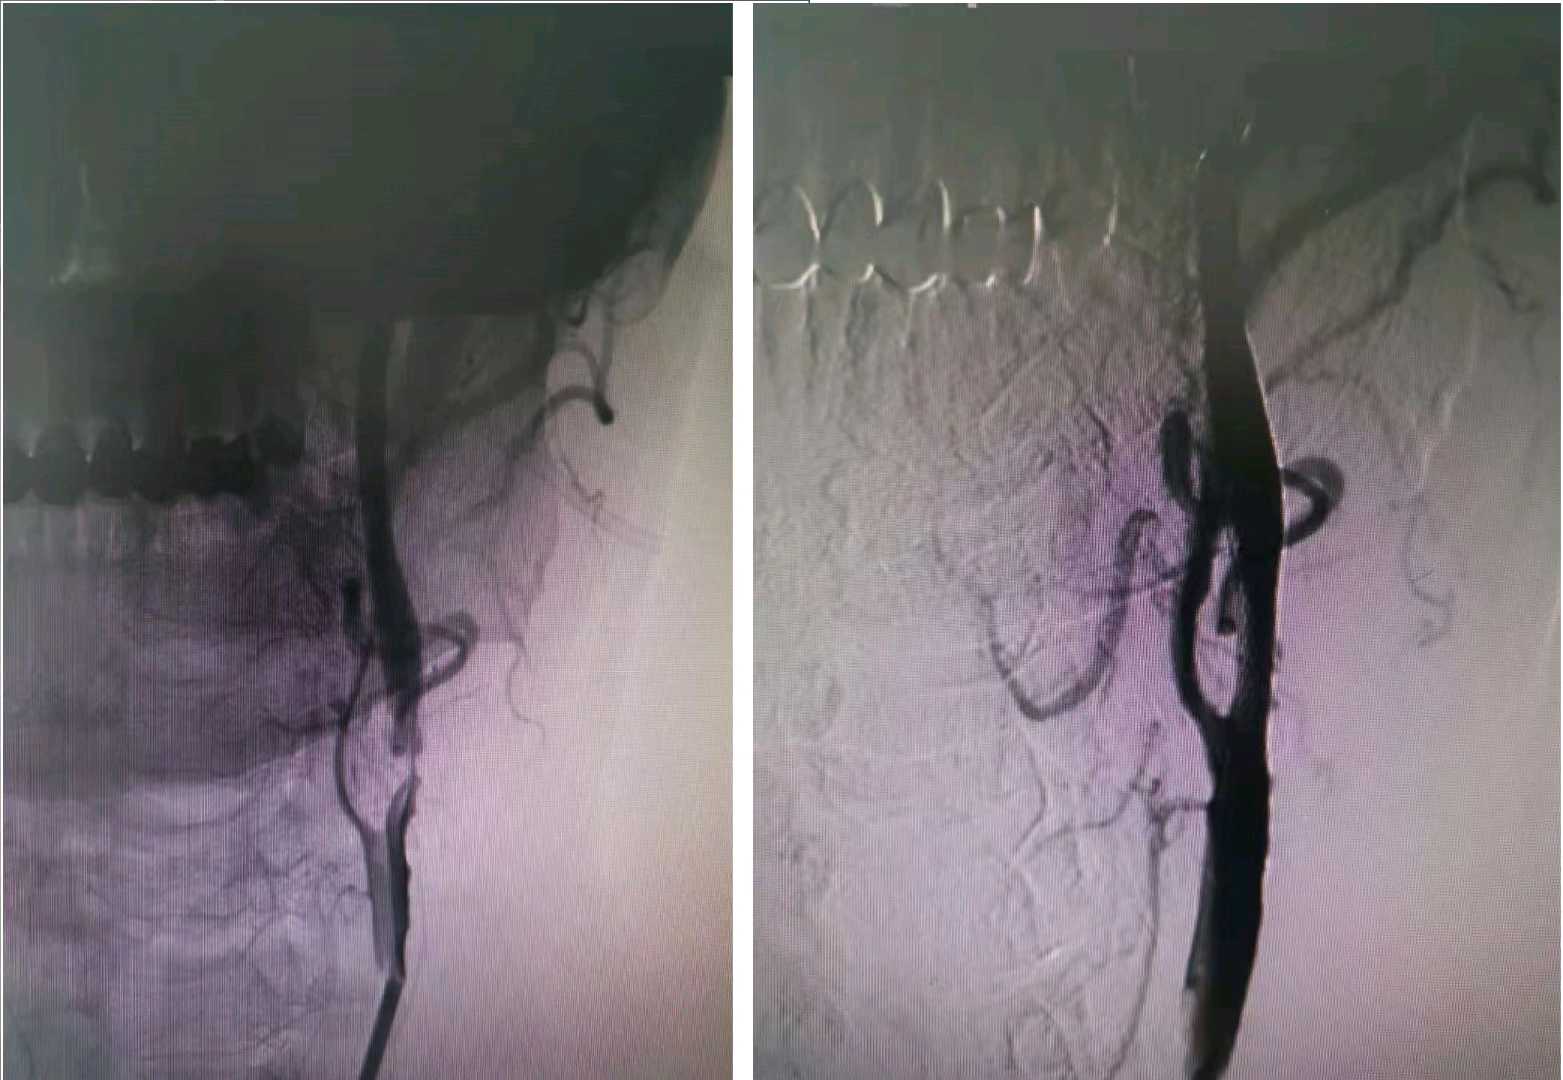

分享本周弓上动脉,左椎动脉保护下行左锁骨下动脉支架植入术。

左锁骨下动脉重度狭窄,病变短段,19㎜长支架搞定。

左侧颈动脉重度狭窄,予一枚wallstent支架解决问题。